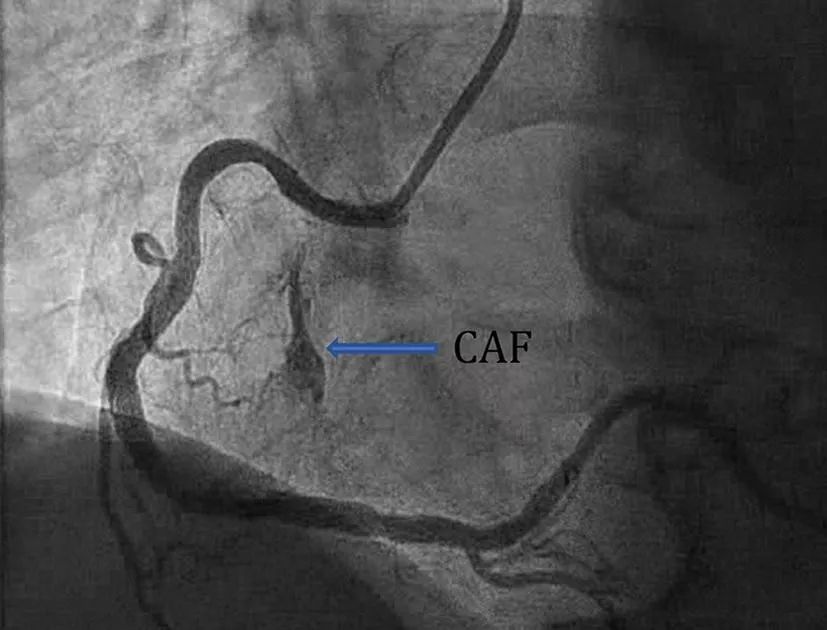

在进行冠脉造影时,有时可以见到下面这些图像。

图1 回旋支-左心室CAF

与冠心病一样,冠脉造影是诊断CAF的金标准。造影显示解剖结构较清晰,对小CAF显示较好,同时也可以评估CAF对血流的影响。但是对结构复杂的CAF,造影颇为吃力,有报道称造影对复杂CAF结构的诊断正确率仅为35%-50%,这时需要CT等其他影像手段协助。